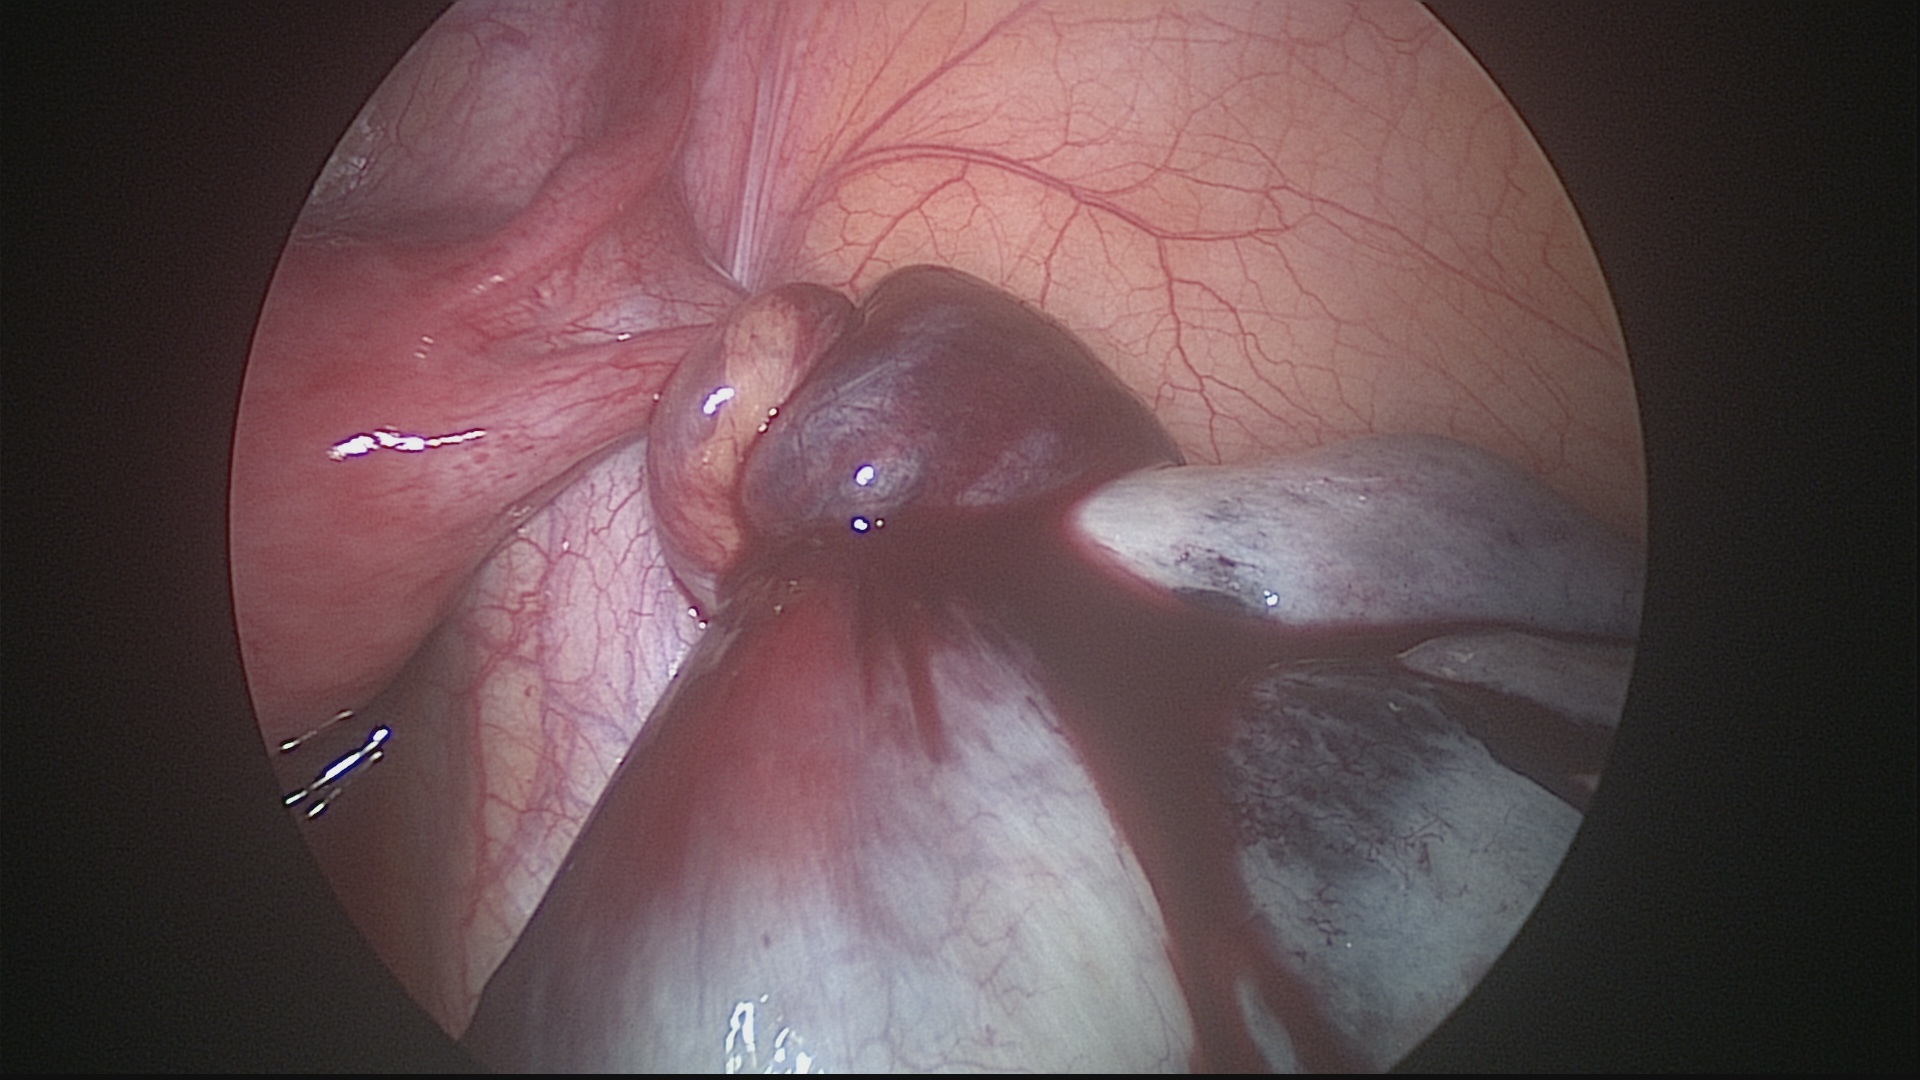

Ocorre quando um cisto de ovário torce seu pedículo, impedindo a passagem de sangue para o órgão e, consequentemente, causando isquemia do tecido ovariano, associada a dor intensa na parte baixa do abdômen. Caso o diagnóstico seja realizado precocemente, a laparoscopia pode reverter esta torção, preservando o ovário. Em casos de diagnóstico tardio, pode haver necrose do tecido ovariano e o ovário deverá ser retirado pela laparoscopia.